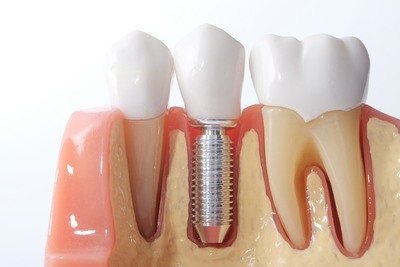

Implantologia L’implantologia dentale è un insieme di tecniche chirurgiche volte a riabilitare le naturali funzioni in un paziente affetto da edentulismo (mancanza di denti) parziale o totale, attraverso impianti dentali metallici e non. Questi impianti, inseriti chirurgicamente nell’osso della mandibola o della mascella, hanno lo scopo di consentire la connessione di protesi, fisse o mobili, atte a restituire al paziente la funzione masticatoria. Al giorno d’oggi, la maggior parte degli impianti è realizzata in titanio. |

La chirurgia implantare si occupa delle emergenze chirurgiche, come le emorragie, gli ascessi ed i traumi, e delle procedure relative alle estrazioni complesse, alla rimozione di cisti mascellari, alle disinclusioni di tipo chirurgico-ortodontico ed alla rimozione delle neoformazioni dei processi alveolari.

Il ruolo della chirurgia implantare è di primaria importanza, in quanto supplisce al reintegro di elementi dentali mancanti nel paziente per la fissazione di protesi fisse e mobili.

Grazie alla chirurgia implantare, inoltre, in caso di tessuto osseo carente, è possibile ricorrere alla ricostruzione ed alla rigenerazione della parte trattata, impiegando materiali biocompatibili o autologhi, cioè appartenenti al paziente stesso, con notevoli potenzialità riparative.